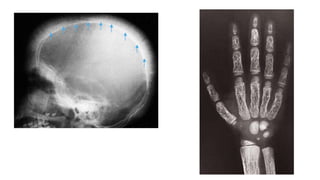

Eosinophil granuloma

🠶 Isthe mildest and most frequent form of Langerhans

histiocytosis.

🠶 It occurs in children and young adults

🠶 Lytic lesions which may be single or multiple, most frequently in

the skull, pelvis, femur and ribs.

🠶 May have the features of an aggressive lesion, or well defined

and may have a sclerotic rim.

🠶A periosteal reaction issometimes seen.

Eosinophil granuloma 🠶 Isthemildest and most frequent form of Langerhans histiocytosis. 🠶 It occurs in children and young adults 🠶 Lytic lesions which may be single or multiple, most frequently in the skull, pelvis, femur and ribs. 🠶 May have the features of an aggressive lesion, or well defined and may have a sclerotic rim. 🠶A periosteal reaction issometimes seen.

🠶The hallmark of hyperparathyroidism issubperiosteal

bone resorption, particularly at the radial side of the

middle phalanges and at the tips of the terminal

phalanges.

🠶Hemolytic anemia:

🠶Marrow hyperplasia: phalanges, skull: hairon end